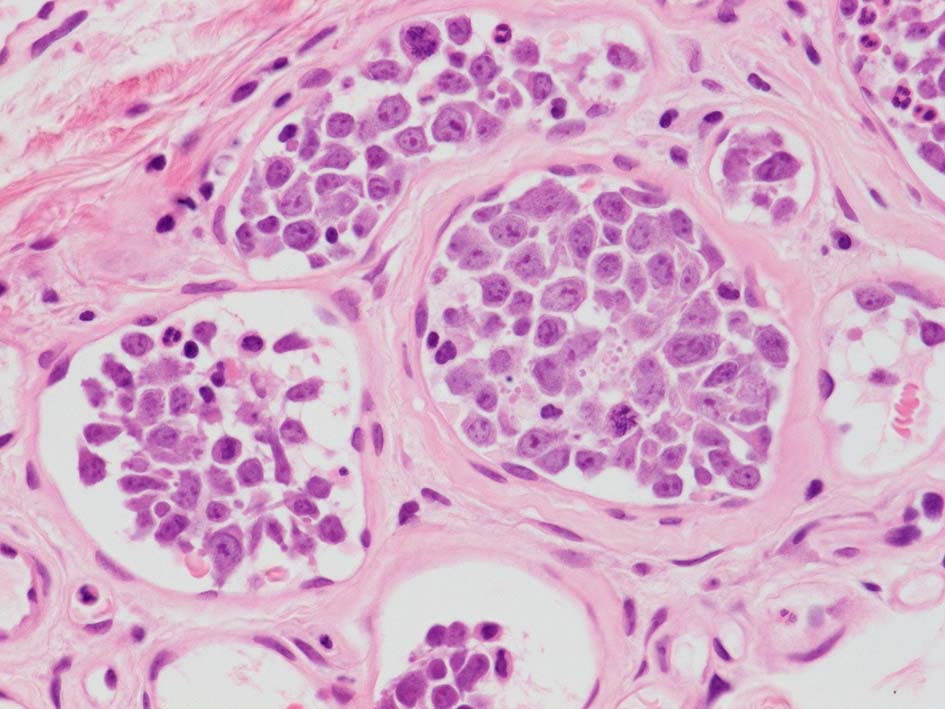

腎臓;糸球体係蹄内に腫瘍細胞が増殖するほか細腎動脈にもみとめられる。

生検組織により血管内腔を塞ぐように大型異型リンパ球が増殖していることを確認することが診断の要件である。血管内増殖の病変分布が本病型では, 脳, 肺, 肝, 腎, 副腎, 皮膚, 骨髄など特有である。しかし大細胞型B細胞リンパ腫にはこのような臓器を選択的に侵襲するが, 血管内腔には増殖しないものがあることに留意が必要である。

皮下脂肪織,細血管内の腫瘍細胞. 大型多型細胞より若干小さめの腫瘍細胞も認められる. CD20を先に染めておくと病変の有無がわかりやすい. HEだけで安易に「病変なし」としないほうがよい.